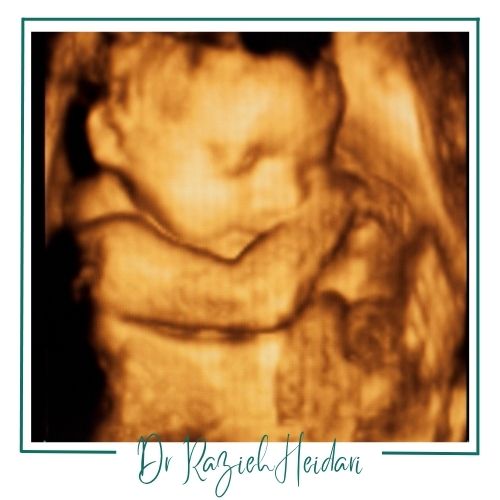

سونوگرافی داپلر جنین

این روش یک روش تصویربرداری پیشرفته است که با استفاده از امواج صوتی جریان خون در جنین و جفت را بهصورت رنگی نمایش میدهد. این ابزار به پزشکان کمک میکند تا مشکلاتی مانند کاهش رشد جنین، فشار خون بالا در بارداری و اختلالات خونرسانی به جنین را شناسایی کنند. معمولاً در بارداریهای پرخطر و در سهماهه دوم و سوم بارداری انجام میشود. این روش به ارزیابی دقیقتر سلامت جنین و تصمیمگیریهای درمانی بهتر کمک میکند.